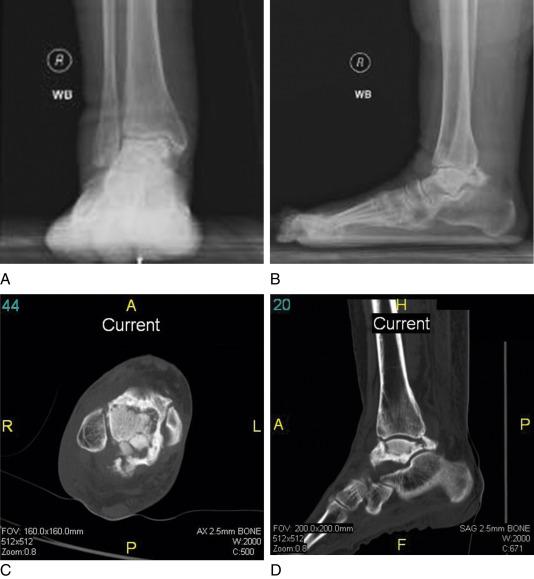

• Failed TAA; case 1: (A) anteroposterior (AP) and (B) lateral left ankle images of a 59-year-old female 12 years post-TAA for traumatic arthritis. This individual complained of pain and was unable to walk for exercise. Note: in the lateral view (B) the patient bears weight, primarily through the forefoot. She is unable to weight bear through her hindfoot due to a fixed, plantar flexed ankle position ( Fig. 61.1B ).

FIG. 61.1

• Osseous necrosis of the talar body; case 2: a 72-year-old female with progressively debilitating right ankle pain. Bracing improved neither pain nor function. AP and lateral weight-bearing films demonstrate sclerotic changes in the talar body and subchondral cyst formation in the tibial plafond ( Fig. 61.2A–B ). Computed tomography (CT) imaging demonstrated sclerotic changes and subchondral fracture involving the talar body ( Fig. 61.2C–D ).

FIG. 61.2